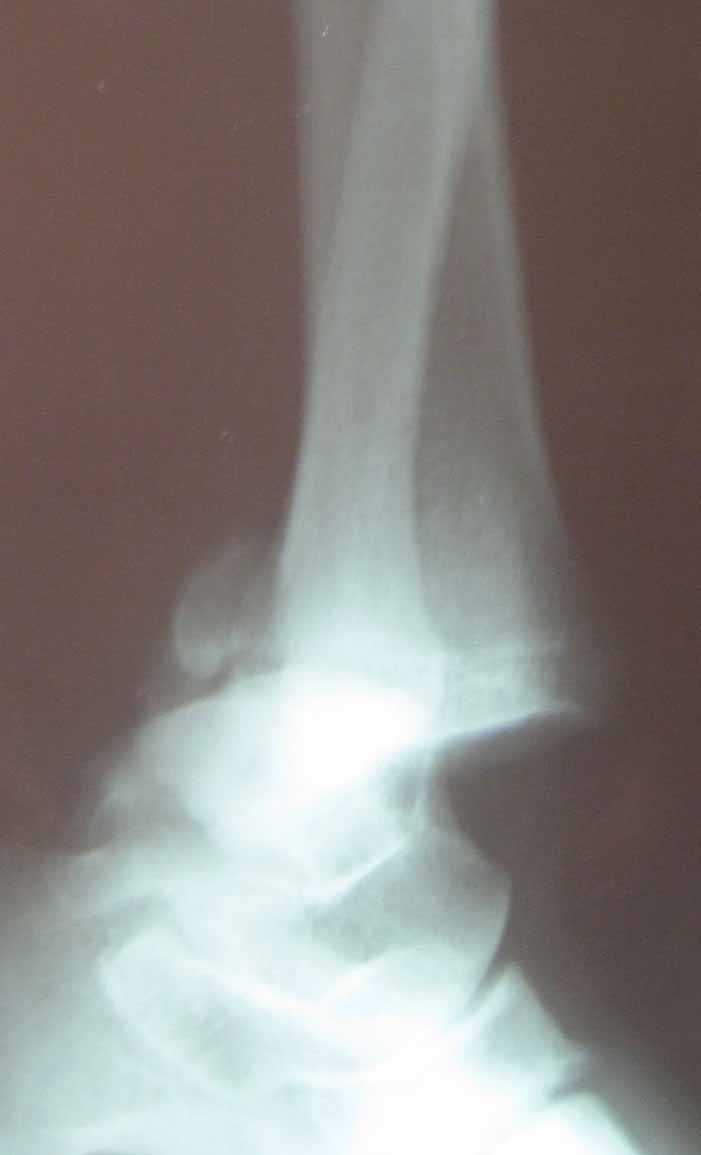

Имя     : 13.jpg

Тип     : image/jpeg

Размер  : 35184 байтов

Описание: отсутствует

Url     : http://weborto.net:8080/pipermail/ortho/attachments/20101026/e044de93/attachment-0002.jpg